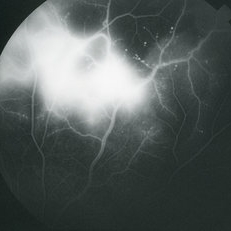

Posterior pole of the left eye of a 23-year-old Vietnamese female with Eales Disease; V.A.= 20/25-2.

Imaging device: Topcon VT-50

Condition/keywords: Eales disease